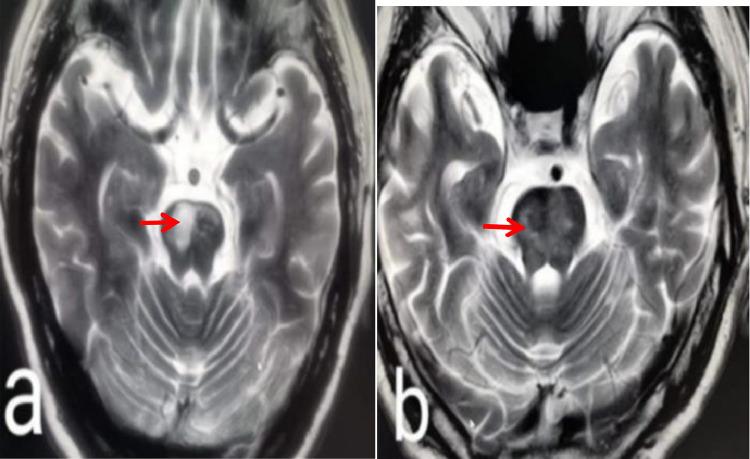

This study used a 3.0T high-resolution magnetic resonance imaging approach to explore basilar artery plaque characteristics in patients suffering from acute isolated pontine infarction.

30 consecutive patients suffering from acute isolated pontine infarction were enrolled in this study and underwent examinations including high-resolution MRI assessment of the basilar artery within 7 days following infarction.

The basilar artery plaque burden of 16 patients with paramedian pontine infarction was 0.26±0.085, while the reconstruction index and enhancement rate index values in these patients were 1.097±0.133 and 1.750±0.447, respectively. In the 14 patients suffering from deep pontine infarction, these three values were 0.21±0.055, 0.896±0.223, and 1.285±0.611, respectively.These values differed significantly when comparing patients suffering from paramedian pontine infarction to those suffering from deep pontine infarction.

This study suggests that the characteristics of basilar artery plaques differ between the two subtypes of pontine infarctions, which may account for the differences in prognosis associated with these two infarct subtypes.